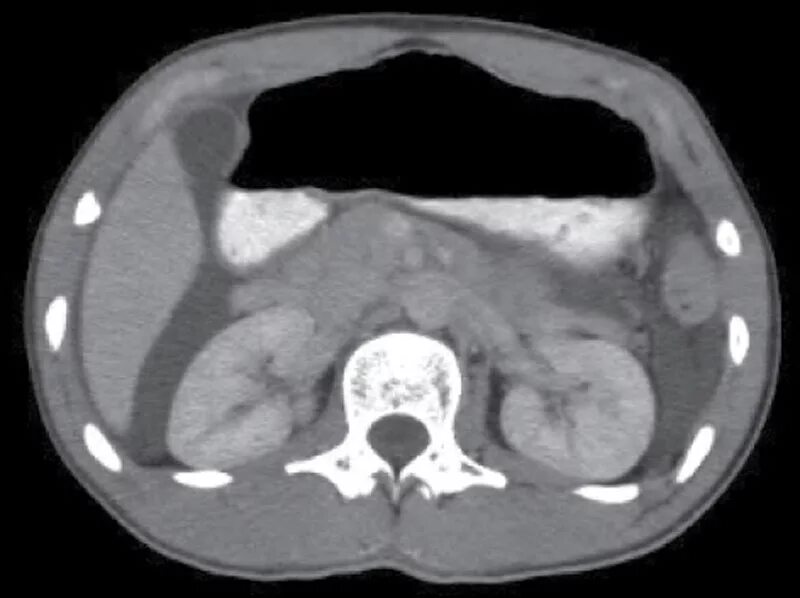

Асцит в малом тазу